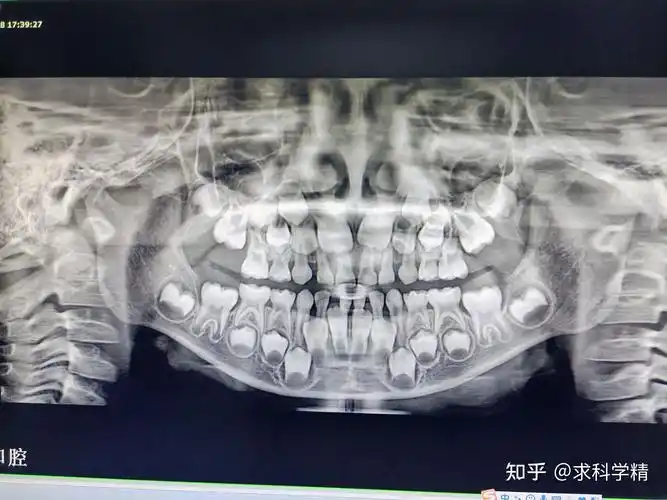

牙片有哪些种类和牙ct有什么区别什么情况下要拍牙齿ct

对育儿经历不足,一直躺着吸奶瓶至4岁,出现牙齿反合,配上ct,5岁半做的

牙齿ct照

本来只是做个检查 现在可怎么办?

结合ct后综合评估了她的牙齿情况,右下的智齿距离神经很近,拔牙风险